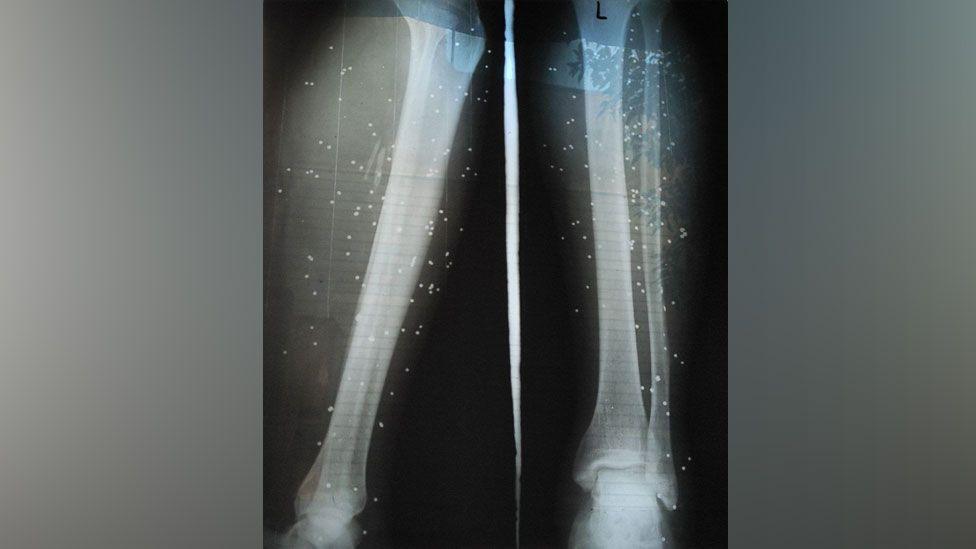

An X-ray showing birdshot in the legs of a wounded protester in Iran